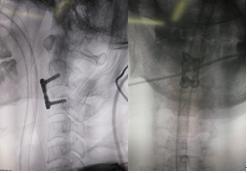

术中照片

术后影像学资料